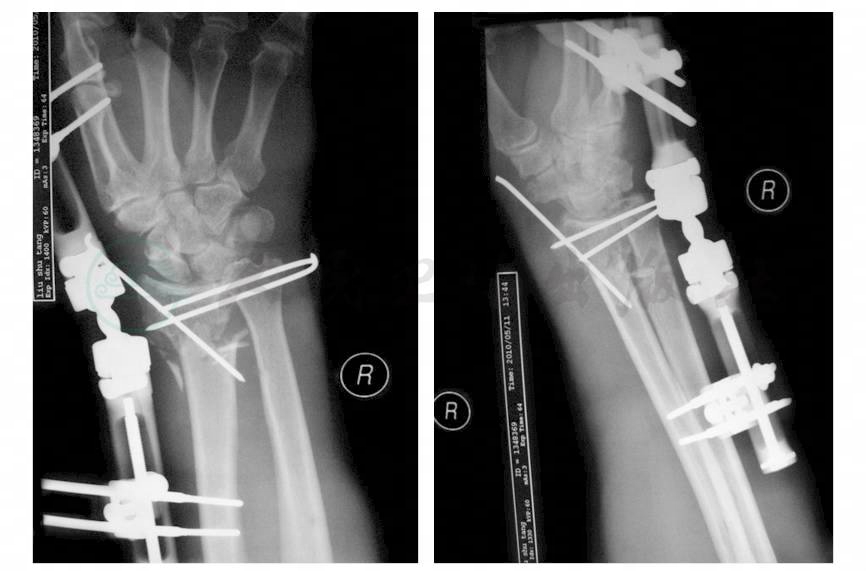

患者,男性,76岁。患者入院前2小时在家中不慎右腕部被狗咬伤,即感右侧腕部剧烈疼痛,流血不止,伴右腕部畸形,活动受限。就诊于北京大学人民医院急诊,行X线检查提示为“右桡骨远端骨折”,遂入院进一步治疗。既往15年前因腹外疝行手术治疗。查体:右腕部夹板固定及敷料包扎,可见较大量血性渗出,拆开敷料可见腕部掌侧、背侧及手背多个大小不等、深浅不一的创口及皮肤缺损。腕部明显肿胀,下尺桡关节脱位,右腕尺偏畸形明显。尺侧5cm长伤口,尺骨头外露。桡背侧两处各有5cm伤口,活动出血,肌腱外露,手背多发较小皮肤裂伤。右手指端、小指、虎口区感觉无明显减退,皮温稍降低,桡动脉、尺动脉搏动良好,指端血运尚可。辅助检查:X线片(急诊):右侧桡骨远端干骺端粉碎骨折、向尺侧完全移位,下尺桡关节分离(图1)。

图1 术前腕关节正侧位X线片